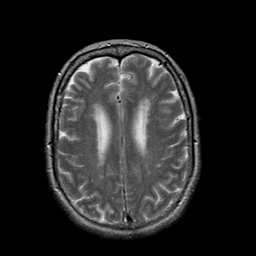

The main limitation of the above-mentioned methods is their dependency on a large number of paired images, i.e., both images belong to the same patient, perfectly registered for training [27], which is difficult to obtain. If the registration has a local mismatch between different modalities, the learning models would generate irrelevant images. To overcome this issue, Zhu et al. [49] proposed cycleGAN to synthesize images from unpaired data in an unsupervised manner. Although cycleGAN has shown remarkable results in reconstructing identical images to the real input, e.g. CT-to-CT, it can not be directly used to synthesize samples from another modality, e.g., MR-to-CT, as there are no direct constraints between real source and synthetic images [39]. For example, Zhang et al. [46] alleviated this issue using an additional loss to force the generated images to be the same as the real ones. Later, SC-cycleGAN [39] defined a structure-consistency loss into the cycleGAN. Specifically, modality-independent neighborhood descriptor (MIND) [9] and a position-based selection strategy is used as structural features and slice selection, respectively. Moreover, several studies conducted bidirectional prediction, i.e., synthesis of CT images from given MR images and vice versa [38, 1]. In addition, many cycleGAN-based methods have been proposed for medical image synthesis from unpaired data [10, 29, 3], but these methods only used the basic discriminator. The basic discriminator only utilizes images in the target domain, while we discovered that using reference images from only the target domain leads to a problem, as shown in Fig. 1 and 2.

In this paper, we propose a bidirectional learning model, known as dual contrast cycleGAN (DC-cycleGAN), for medical image synthesis from unpaired data. Specifically, a dual contrast (DC) loss is formulated that leverages the advantage of samples from the source domain as negative samples to indirectly build constraints between real source and synthetic images via discriminators, and synthesize images more related to the target domain by enforcing the synthetic images to fall far away from the source domain. In addition, structural similarity index (SSIM) [35] and cross-entropy (CE) [48] are integrated into the DC-cycleGAN structure to avoid disappearing gradient information that is caused by a mean absolute error (MAE) and synthesizing irrelevant images. SSIM considers luminance [35] and CE converges fast as its back-propagation error is less than MSE [28]. As can be seen in Figs. 1 and 2, using SSIM and CE with dual contrast can generate more clear and accurate MR images as compared with that of MAE and MSE, and SSIM and CE without dual contrast loss. Although both SSIM and CE with dual contrast and without dual contrast generate similar CT images, SSIM and CE with dual contrast quantitatively generate better images as shown in Table 4. The experimental results indicate that DC-cycleGAN is able to consider more complex features such as structure in synthesizing images and produce remarkable results as compared with other state-of-the-art methods reported in the literature.

Tables 3 and 4 show the results of MR and CT synthesis, respectively. As can be seen, all components play vital role in both tables. SSIM & CE (w) performs significantly better than other losses in synthesizing MR images. This also can be seen visually in Fig. 1. In contrast, SSIM&CE (w) performs slightly better than SSIM&CE (wo) in synthesizing CT images, both generate more or less similar CT images (see Table 4).